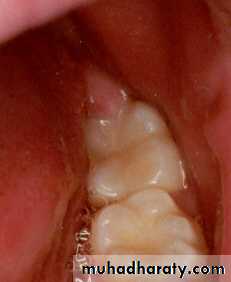

a. Clinical examination

8